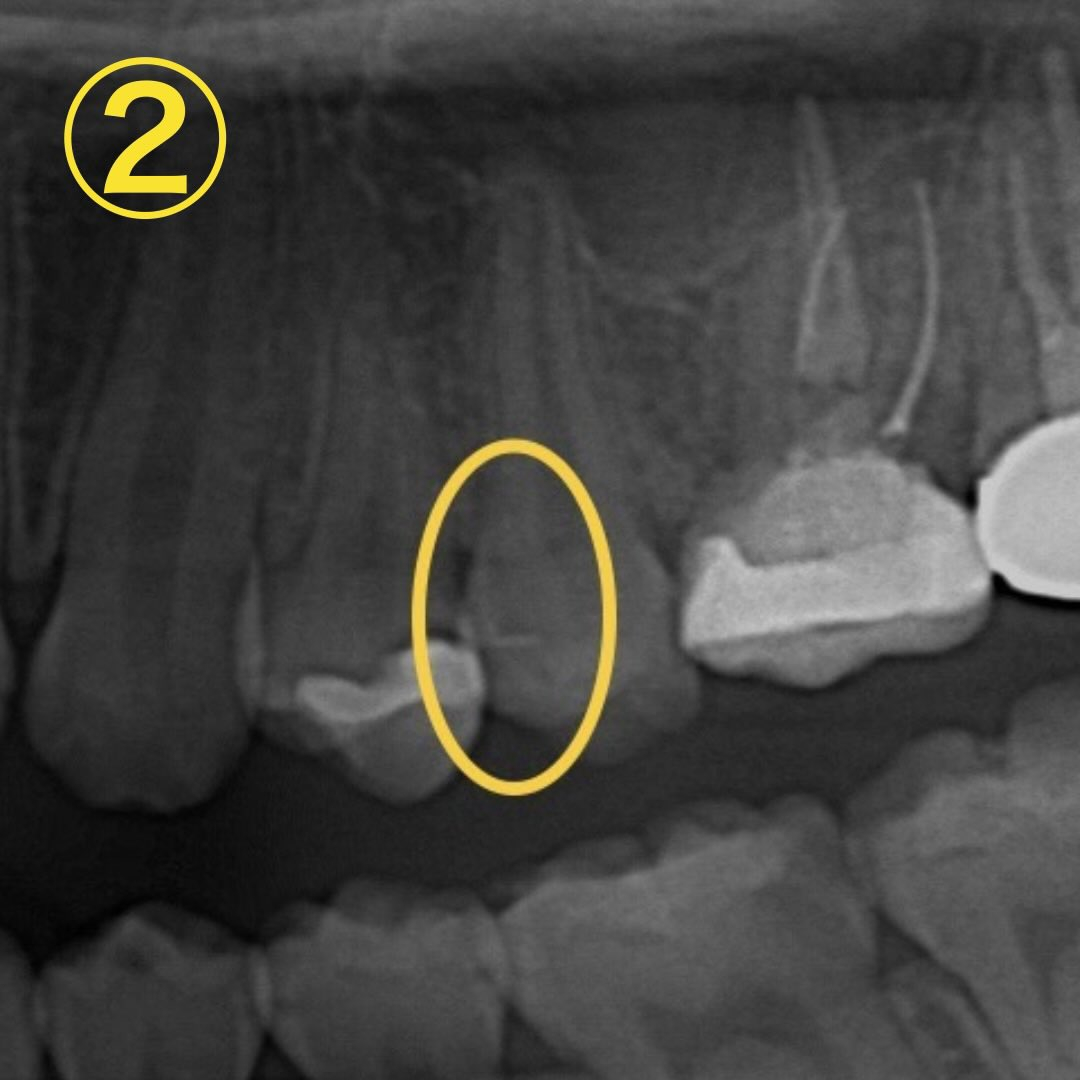

レントゲンを撮影すると詰め物の裏側に虫歯があるのが分かります🔎→画像②、黄色く囲った黒い部分です👀